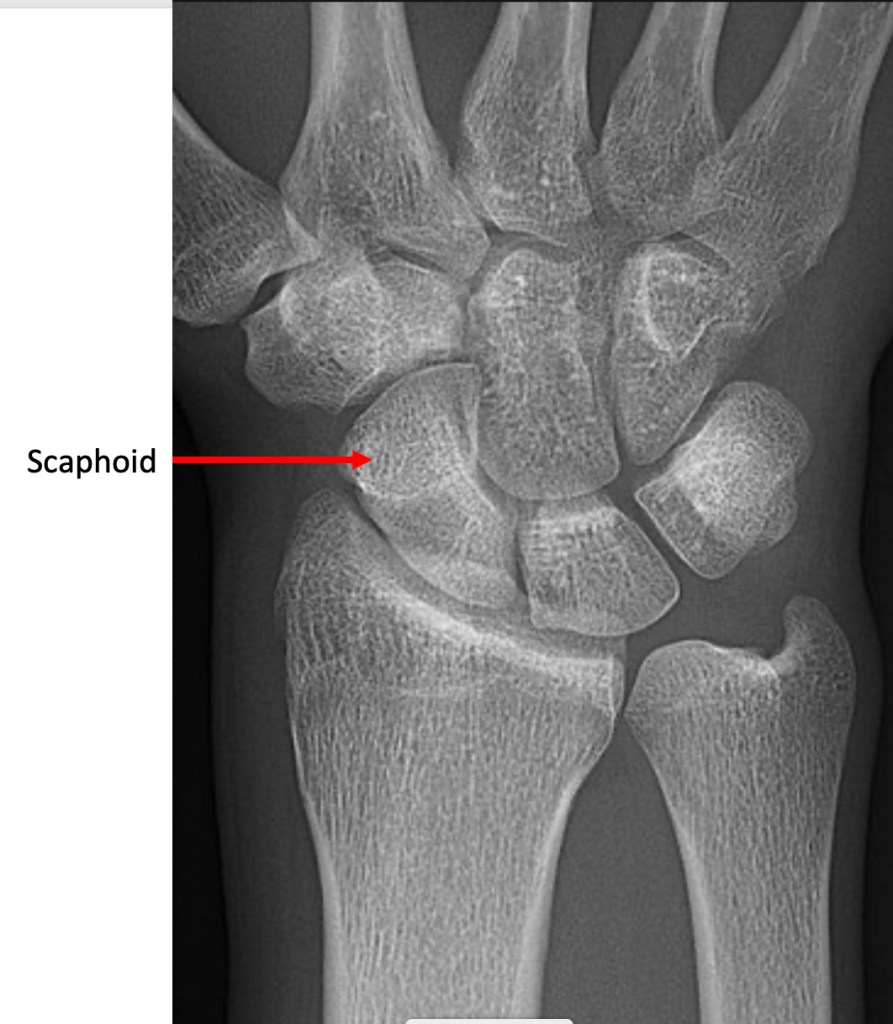

The scaphoid is the most commonly injured bone within the wrist, but frequently difficult to assess on X-rays. In addition, other damaged or bruised structures around the wrist can give similar symptoms. The term “query scaphoid” injury is a term given when symptoms and signs are consistent with a scaphoid fracture, but the X-ray does not show a fracture.